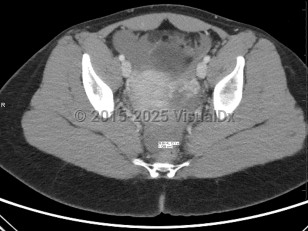

Ruptured ectopic pregnancy can result in intraperitoneal bleeding, uterine hemorrhage, and hemodynamic instability. Development of any of these complications should be considered a surgical emergency and warrants emergent evaluation by a gynecologic surgeon; exploratory laparotomy may be required. Even in the absence of concern for rupture, surgery may be considered, particularly in patients failing or with contraindications to methotrexate, in the setting of heterotopic pregnancy (ectopic pregnancy occurring simultaneously with a viable intrauterine pregnancy; see Look For), or in patients seeking sterilization.

A 2011 consensus statement provides definitions that draw attention to the complexity of evaluating for and diagnosing ectopic pregnancy, with 5 categories based on sonographic findings:

- Definitive intrauterine pregnancy

- Probable intrauterine pregnancy

- Pregnancy of unknown location

- Probable ectopic pregnancy

- Definite ectopic pregnancy